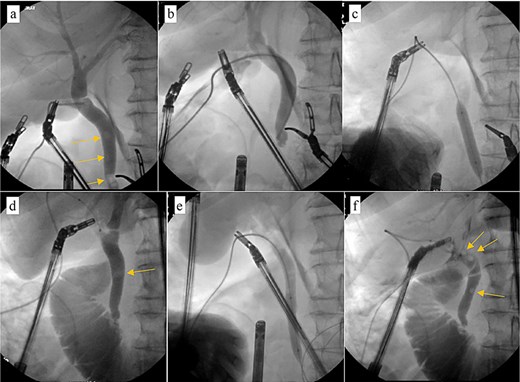

Patient was brought to the OR, induced, and the peritoneum was accessed via optical view trocar. After the critical view of safety was obtained, the cystic duct was partially transected and a 6-French ureteral catheter was threaded through the duct and into the CBD. Initial cholangiogram showed complete obstruction of the distal CBD. A 0.035 guidewire was advanced through the ureteral catheter. The ureteral catheter was then exchanged for a 9 × 40 mm long vascular balloon catheter. The balloon was then centered at the ampulla of vater and inflated to its nominal pressure for 5 min. A small indentation was noticed at the level of the ampulla once the balloon was fully insufflated, as expected. The completion cholangiogram showed prompt evacuation of contrast into the duodenum. However, numerous “floating” filling defects continued to be present (Fig. 4). The decision was thus made to leave a T-tube in place via a 1-cm longitudinal choledochotomy. The incision was reapproximated around the t-tube with interrupted 4–0 PDS. The vascular balloon catheter was removed, the cystic duct was completely transected, and the gallbladder was dissected off the liver bed.

Intraoperative cholangiogram. (a) Initial cholangiogram via 6-fr ureteral stent showing multiple filling defects (arrows). (b) Guidewire passed through the ureteral stent and down to the level of the ampulla of vater, demonstrating complete CBD obstruction. (c) 7 × 40 mm vascular catheter balloon advanced over the guidewire and through the ampulla of vater. Dilated to nominal pressure. (d) Contrast now able to leave the CBD and into the duodenum. Residual “floating” filling defects still seen (arrows). (e) Vascular catheter exchanged for a 9 × 40 mm balloon and dilated to nominal pressure. (f) Completion cholangiogram shows brisk outflow of contrast with residual filling defects (arrows).

Patient was discharged home on POD 7 following IV antibiotic completion (Fig. 5). Patient was seen in the ER 1 week later for drainage around the T-tube. Tube study confirmed resolution of CBD obstruction and the patient was discharged from the ER (Fig. 6).

This case report also outlines early experience in our institution with transcystic common bile duct exploration with antegrade balloon sphincteroplasty as outlined by Bosley et al. [4] This technique represents a significant potential for patient populations that have anatomic alterations that preclude them from getting an ERCP, such as in the bariatric surgery population. In this particular case, there was some struggle with sphincter of Oddi spasm, likely due to insufficient balloon inflation up-time and CBD/Vascular balloon diameter mismatch. Further investigation into this particular modality is certainly warranted.